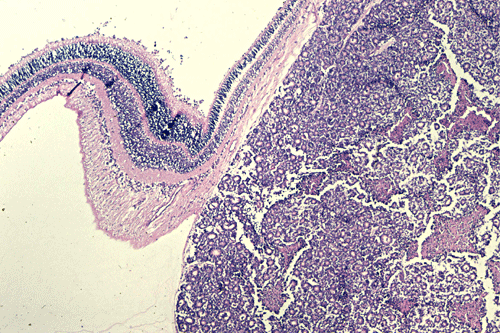

On the whole mount of the globe, there is an exophytic neoplasm that occupies about one-third the volume of the vitreous. The surface of the retina is free of tumor deposition (Panel A). The retina is detached by the mass. There are some pink, necrotic material at the core of the tumor (Panel B). On medium and high-magnification, the tumor is composed of densely packed small cells with hyperchromatic nuclei  without prominent nucleoli. A large number of the cells arrange in rossettes with a well-defined luminal border (Flexner-Wintersteiner rossettes) (Panel C and D). The tumor is confined within the globe and the optic nerve is free from invasion.

The exophytic type grows primarily from the outer retinal surface of the retina towards the choroids and is well illustrated in this case. The tumor will produce an elevation and then a detachment of the retina.  From the choroids, tumor cells invade into the orbit and conjunctiva. Extraocular extension and metastasis will follow.  Neither of these patterns carry a prognostic significance. A mixed pattern that consists of both the endophytic type and exophytic type is perhaps the most common type.

The pathology is typical for that of a small blue cell tumor with morphologic and immunohistochemical features comparable to medulloblastoma, supratentorial primitive neuroectodermal tumors, and adrenal neuroblastomas. Tumor cells have small to medium sized, hyperchromatic nuclei with clumpy chromatin and without prominent nucleoli. Only a small to minute amount of cytoplasm is present.  Mitotic figures are numerous. Retinoblastoma has a striking tendency to undergo necrosis. The tumor cells that are closer to the blood vessels are more likely to remain viable. Calcifications are common findings in the necrosis.  Some of the nucleic acid liberated from these necrotic cells becomes absorbed in the walls of blood vessels giving them a deep blue appearance.